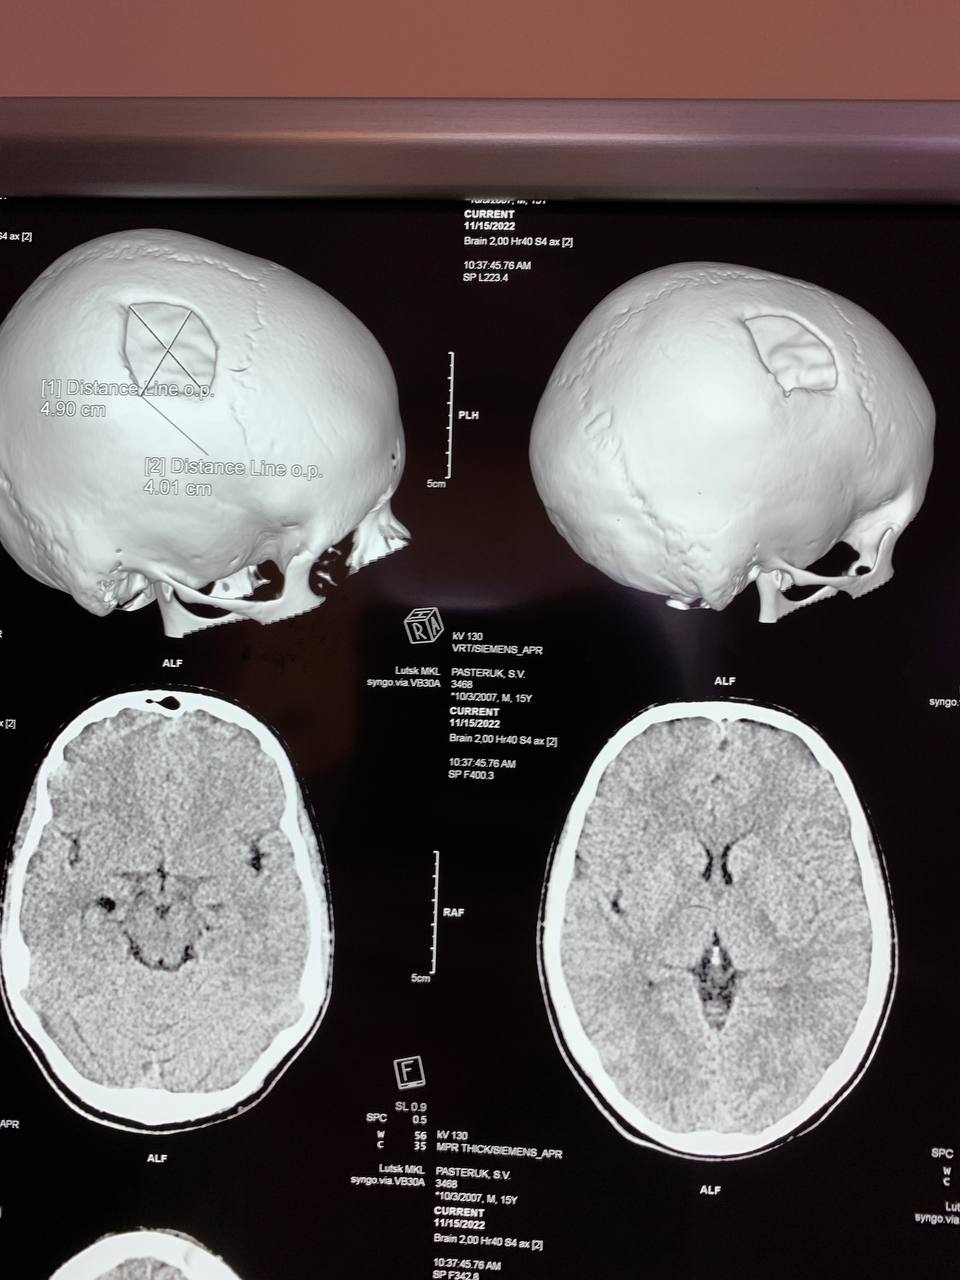

Рівненські лікарі встановили в череп 15-річному хлопцеві з Волині титанову пластину.

«15-річному хлопцю з Волинської області, який дев'ять місяців тому отримав складну черепно-мозкову травму, виконали краніопластику. Пошкоджену частину черепної коробки закрили спеціальною титановою пластиною, яка повторює кісткові структури черепа, захищає мозок від ушкоджень», - йдеться у дописі.

Оперативне втручання провели: лікар-нейрохірург дитячий Сергій Романчук та лікар-хірург дитячий Ігор Сегін.

За словами медиків, операція пройшла успішно, хлопець на третю добу був виписаний додому.